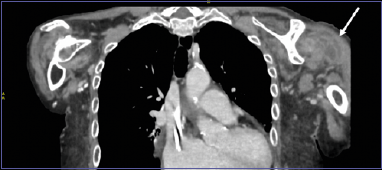

An 85-year-old woman, affected by hypothyroidism, atrial fibrillation, hypertension, cryoglobulinemia, and end-stage chronic kidney disease on hemodialysis, presented to our emergency department complaining of left shoulder pain and functional limitation after a fall 7 days before, without direct shoulder trauma. The patient was apyretic and had had no fever in the previous days. Nevertheless, she had started empiric antibiotic treatment with amoxicillin-clavulanate since the day before upon advice of her family physician for a non-specified infection. The shoulder showed warmness and severe effusion, but radiographs showed only undisplaced posterior fractures of the VII-VIII-IX left ribs. Ultrasound and contrast-enhanced CT scan of the shoulder revealed an intraarticular multilocular fluid collection (Figs. 3-4). Blood exams showed elevated CRP (177 mg/l) without leukocytosis and procalcitonin of 2.02 ng/ml. A joint aspiration was performed, revealing a leukocyte esterase strip ++, 76,530 synovial leukocytes/ul with 92% polymorphonucleates, but negative synovial cultures. A culture negative NGHJSA was diagnosed. The patient was hospitalized and underwent urgent articular open I&D and antibiotic therapy, initially with vancomycin and piperacillin tazobactam for 10 days. During the postoperative days the NGHJSA progressively resolved with a return to a normal pain-free function, but the patient frequently had fever. Intraoperative cultures and the several blood cultures performed during fever episodes were all negative. A transesophageal echocardiography revealed a septic vegetation on the central vein catheter used for hemodialysis, that was subsequently substituted, and the antibiotic therapy was shifted to vancomycin and meropenem for 4 days and meropenem alone for another 14 days, with definitive resolution of the pyretic episodes.

Figure 4.Case 2: coronal contrast-enhanced CT scan showing the multilocular intraarticular left shoulder fluid collection.